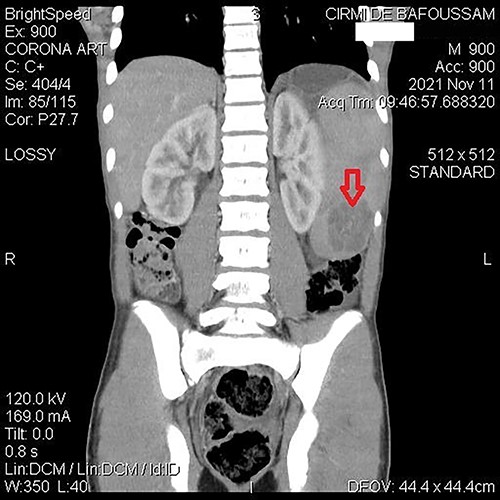

A 15-year-old patient presented with a 3-week history of left upper quadrant abdominal pain with no other symptoms. He had no prior history of pulmonary TB. His vital signs were as follows: temperature = 37°C, blood pressure = 120/78 mmHg, pulse = 84/min, respiratory rate = 15/min, SpO2 = 96% on room air; and physical examination only revealed a mild tenderness in the left upper quadrant with the tip of the spleen expanding to the umbilicus. An abdominal ultrasound (US) followed by a computed tomography (CT) scan revealed a heterogeneous splenomegaly with multiple cystic masses in the spleen and the tail of the pancreas (Figs 1 and 2). Laboratory exams showed a white cell count of 2600/mm3, hemoglobin of 11.4 g/dl, C-reactive protein (CRP) of 34 mg/l, hemoglobin electrophoresis AA and negative malaria and HIV tests. We suspected a primary or secondary malignancy of the spleen, like a lymphoma or a metastatic pancreatic carcinoma. The other diagnoses were tropical splenomegaly and splenic infarct. We performed a distal pancreatectomy with splenectomy, and histopathological analysis revealed caseating granulomas of the spleen (Fig. 3) with no malignancy suggesting TB. Further, a Ziehl-Neelsen stain of the specimen showed acid fast bacilli (AFB). The patient received anti-TB drugs, had an uneventful post-operative course and was discharged on post-operative day 7. On the first month follow-up visit, he reported marked improvement of his symptoms.

Abdominal CT demonstrating a cystic mass in tail of the pancreas (top arrow) and the tip of the spleen (bottom arrow).